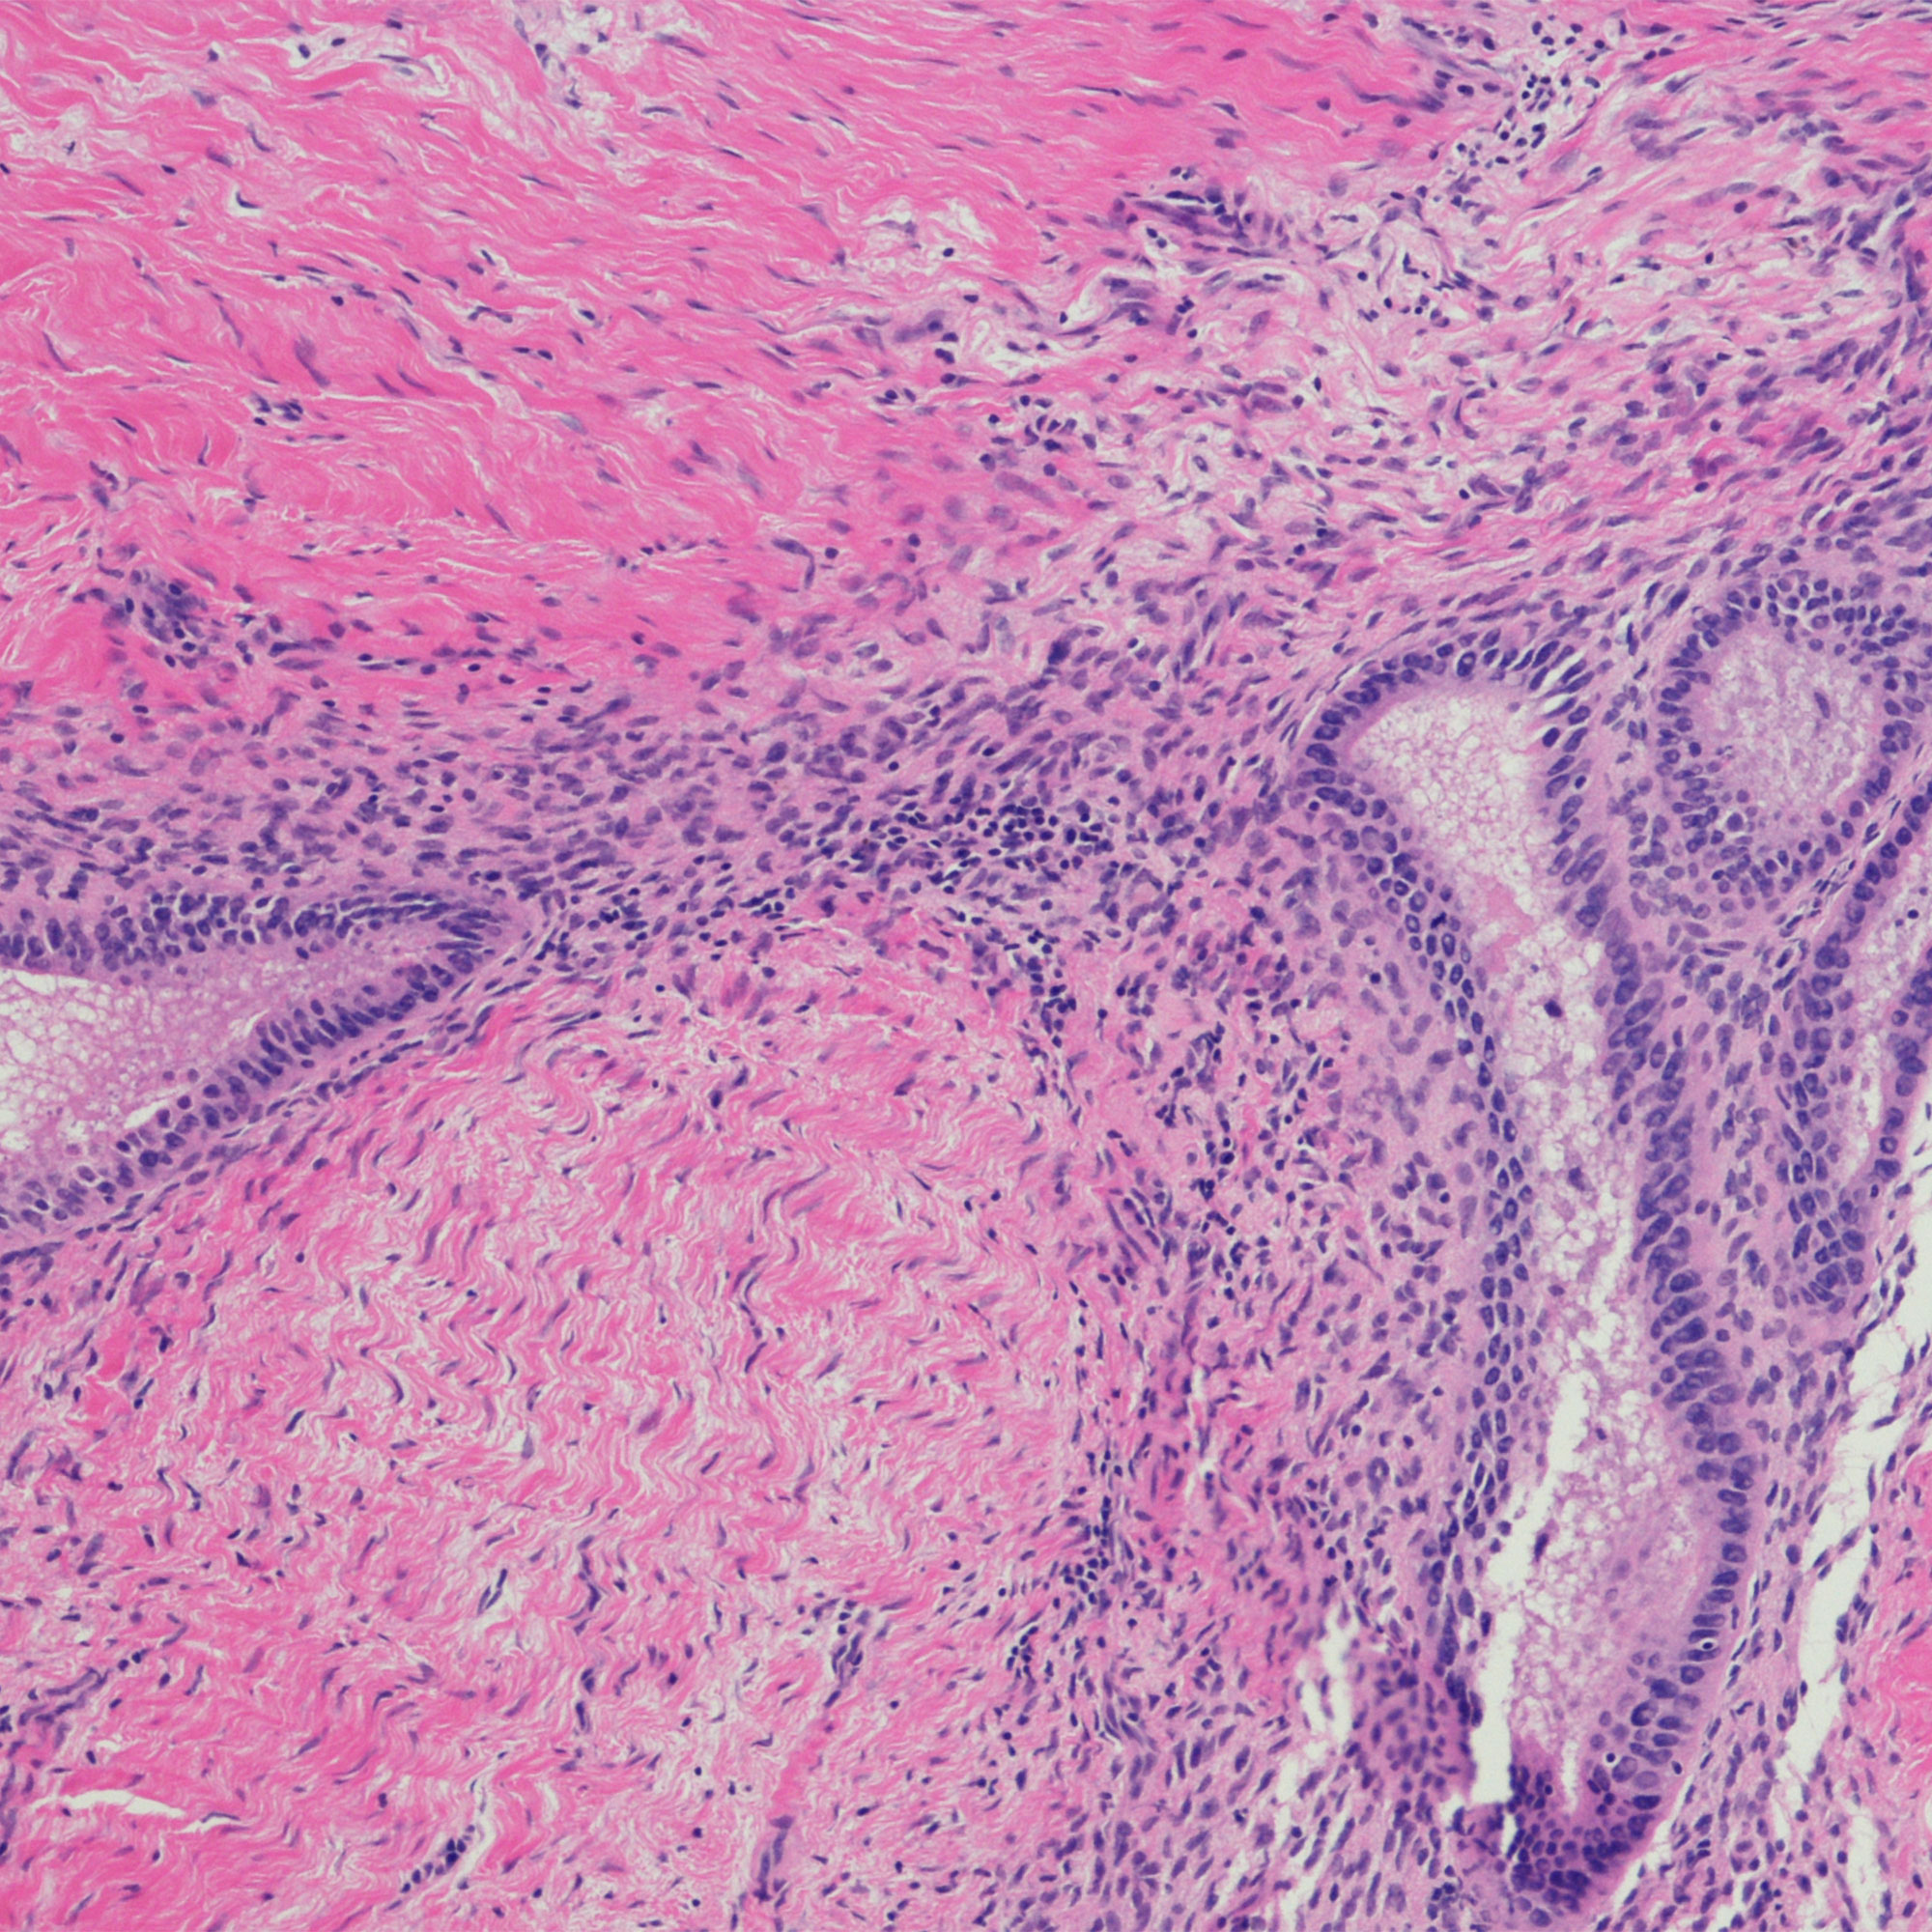

广泛的症状可能表明你有子宫内膜异位,但没有办法知道除非你寻求评估由医学专业。“子宫内膜异位症可以认为基于别人的症状,但真正的诊断只是由外科诊断和组织分析,“蔡博士说。所以如果你经历任何上述迹象,这是明智的去检查一下。“大多数妇产科和内科初级保健提供者并不精通,所以提前咨询专家,”马丁·路德·金博士建议。

诊断你,你的医生可能会问你关于不同的症状,如上面所列的那些),可能包括执行其他测试腹腔镜手术和组织分析,证实子宫内膜异位,蔡博士说。你的医生会开治疗为你endo和减少痛苦的症状和保护你的目标对其他离开endo未经处理的长期风险。这些风险包括不孕和患卵巢癌的几率增加。如果你认为你可能有子宫内膜异位症,今天跟你的医生。排除其他条件,得到一个精确的诊断是第一步的感觉更好。